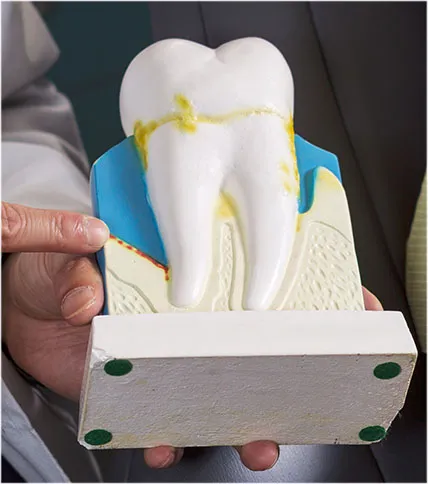

Endodontics in [practice:neighbourhood]

Root canal treatment saves a damaged tooth from being lost and prevents potentially dangerous infections. Learn more about this often-misunderstood but important procedure.